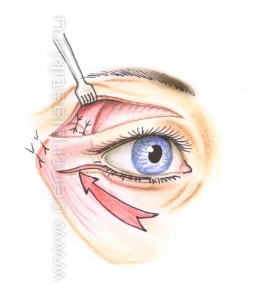

Рис. 9 Через боковую часть разреза выполняется отделение надкостницы от костей в проекции средней зоны лица вниз до крыла носа, обычно для этого используются эндоскопические инструменты. Рис. 11 Мобилизованные ткани прошиваются в верхненаружном углу и фиксируются к надкостнице выше наружного угла глаза. Рис. 12 Выполняется миопексия (фиксация мышцы окружающей глаз) Рис. 13 и кантопексия (фиксация наружного угла глаза), Рис. 14 затем удаляется избыток кожи Рис. 15. Этим достигается правильное положение глазной щели и удается добиться разглаживания мелких морщин. В конце операции кожная рана зашивается косметичным внутрикожным швом.

Рис. 13

Рис. 14

Рис. 15 С помощью подтяжки средней зоны лица удается получать гармоничное омоложение всей параорбитальной области (области вокруг глаз) и средней зоны лица, особенно у тех, кто имеет выраженные возрастные изменения. Кроме того, прямой вертикальный подъем тканей средней зоны лица (против вектора старения) и редрапировка мышцы окружающей глаз, выполняющиеся в ходе этой операции, приводят к более приятному и естественному внешнему виду лица чем, при подтяжке этой области из височного доступа. Рис. 16.